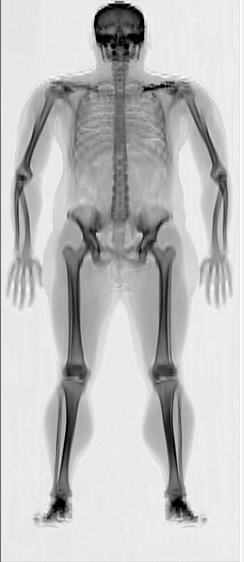

• During a DEXA  scan, you'll lie comfortably on a table while a scanner arm passes over your body and the table moves. It emits low-dose X-rays, which are absorbed differently by bones, fat, and lean tissue. The scan lasts 5-7 minutes